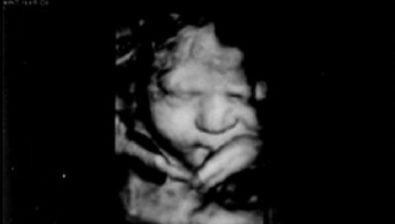

Ultrasound at 34 Weeks

Inside your uterus, you have a little spy. A little fly on the wall, per se.

Your baby’s senses have been active for a while, so he/she can hear what you’re saying and what those in proximity to you are saying.

Now would be perfect time to sing and read to your baby. Studies have shown that babies remember what they hear during their time in the womb.